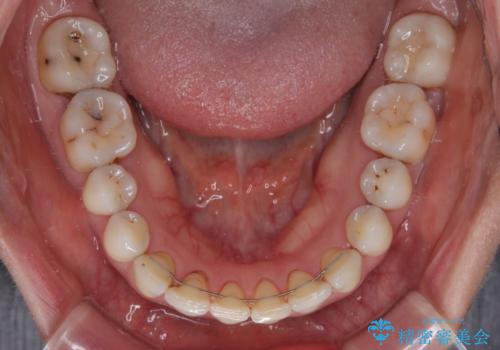

- 隙間の空いた前歯をセラミッククラウンで補隙したところ、歯肉から出血してしまい、何とかしたいとのことで来院された患者様です。

初めは前歯のみの処置で改善を希望されていたため、広範囲に処置範囲を広げることで歯の幅がバランスする治療を提案しましたが、削らなければならない歯が増えてしまうため、患者様と相談して全顎矯正により前歯のスペースを閉じていくこととしました。

不適合なクラウンが装着されていたため、歯周ポケットが深くなっていましたので、矯正治療前に歯周外科処置を行って歯周ポケットを除去し、矯正治療後にオールセラミッククラウンにて補綴治療を行うこととしました。